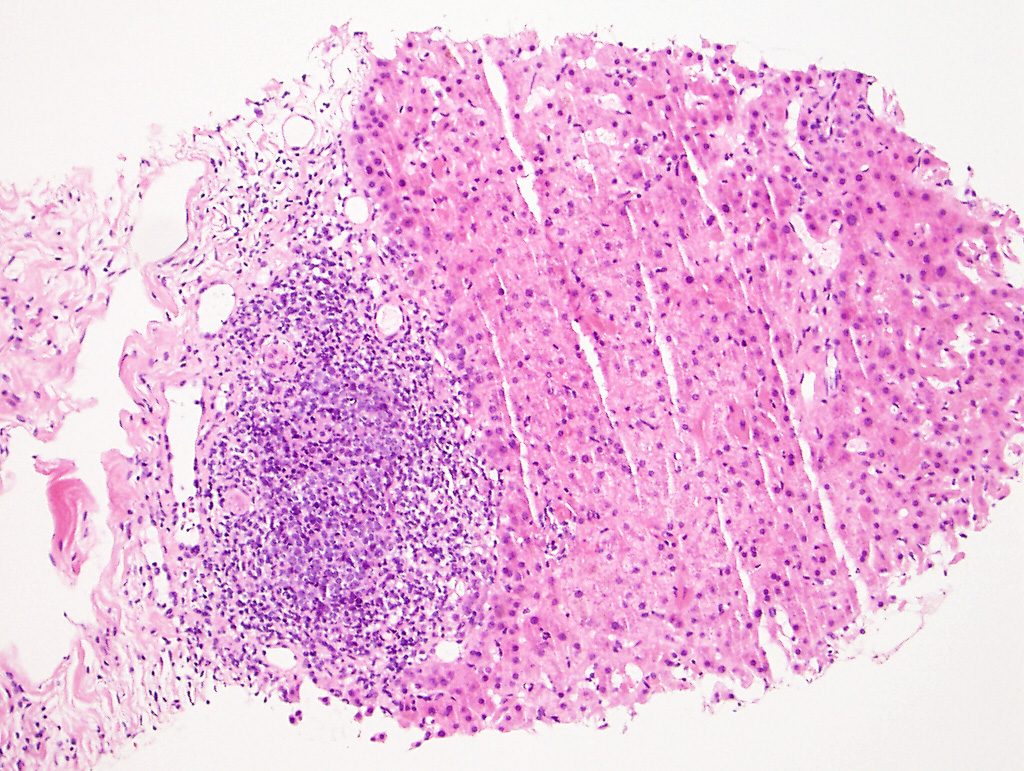

The liver biopsy shows extensive sinusoidal infiltration by bland appearing plump eosinophilic cells with somewhat retractile or granular cytoplasm (Figures 1A and 2A). These cells are positive for CD68 confirming they are histiocytes (Figures 1B and 2B). The histiocytes contain crystalline immunoglobulin kappa highlighted on the Ig kappa and PAS-D stains (Figures 3A and 3B, respectively). Ig lambda was negative.